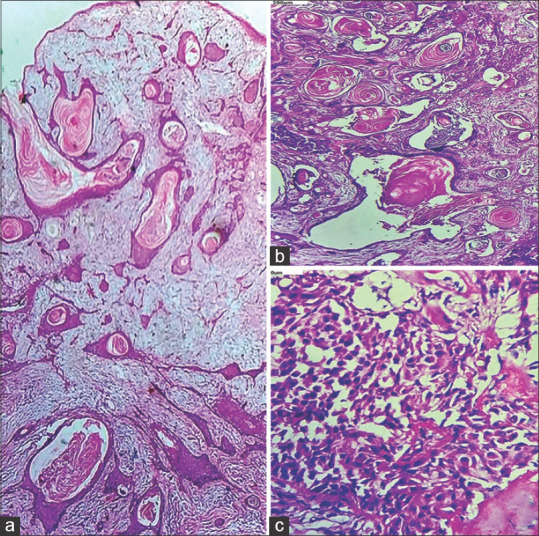

多形性腺瘤是大、小唾液腺最常见的良性肿瘤。组织学多样性是多形性腺瘤的特征。广泛的鳞状皮化生伴角蛋白填充的囊肿很少报道。我们在此报告两例涎腺多形性腺瘤伴增生鳞状化生及角蛋白填充囊肿的病例,并讨论其潜在的诊断缺陷。

Pleomorphic adenoma is the most common benign tumour of major or minor salivary glands. Histological diversity is the hallmark of pleomorphic adenoma. Extensive squamous metaplasia with keratin-filled cysts is rarely reported. Here we present two cases of pleomorphic adenoma with exuberant squamous metaplasia and keratin filled cysts formation in a minor salivary gland and discuss its potential diagnostic pitfalls.